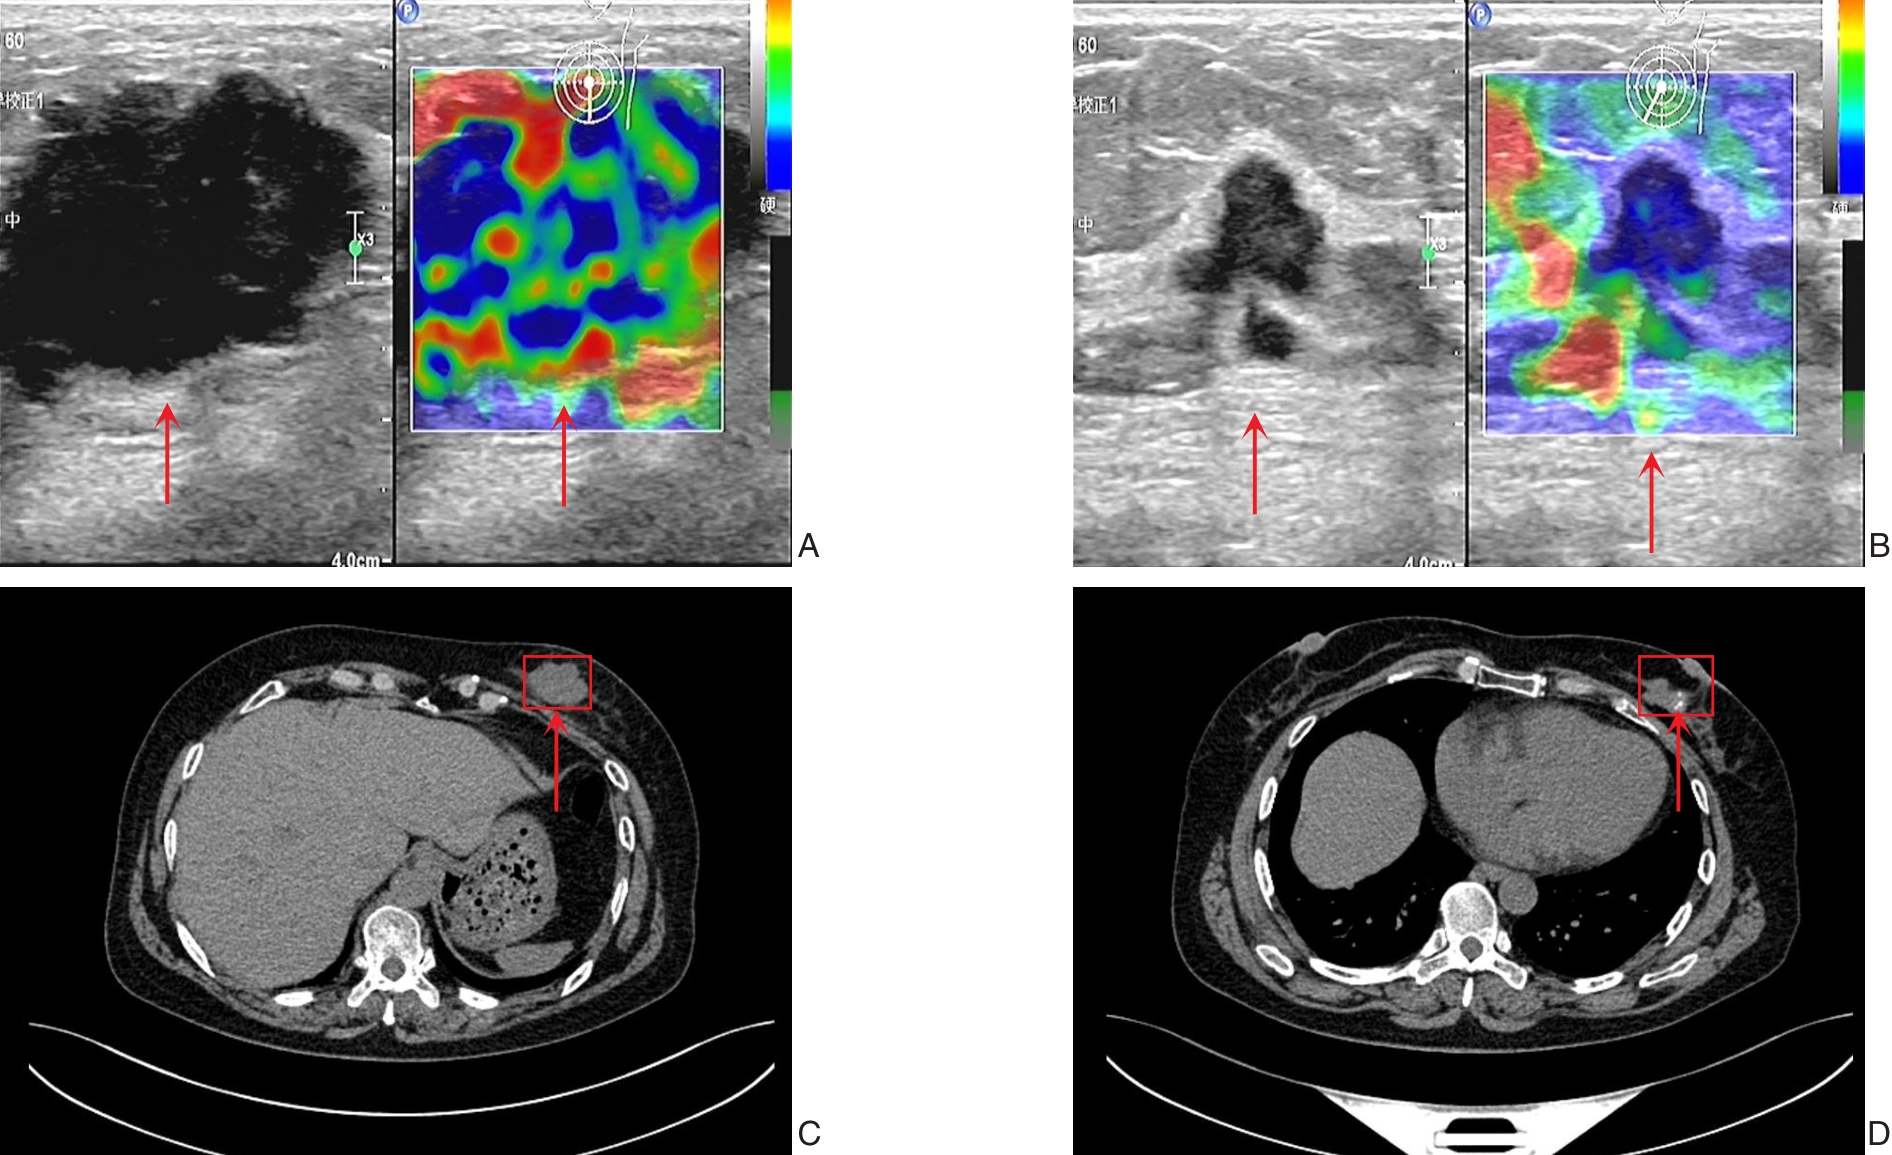

摘要:背景与目的 随着慢性肾脏病发病率的上升,继发性甲状旁腺功能亢进症(SHPT)作为其常见严重并发症之一,日益受到关注。对于药物治疗无效的难治性SHPT,外科切除甲状旁腺是公认的有效治疗手段。然而,由于甲状旁腺位置和数量变异较大,常规手术方式易出现残留,导致术后持续或复发。本研究借鉴甲状腺癌中央区清扫理念,探讨甲状腺系膜扩大切除术(e-TMTE)在SHPT外科治疗中的临床价值,旨在提高切除完整性,降低术后复发率,优化手术流程。方法 选取2018年5月—2024年2月在安徽理工大学第一附属医院、中国科学技术大学附属第一医院确诊的103例SHPT患者为研究对象,其中55例行传统甲状旁腺全切除+自体移植术(tPTX+AT组),48例行e-TMTE+自体移植术(e-TMTE+AT组)。比较两组患者的手术时间、术中出血量、术后1 d引流量、术后住院时间、甲状旁腺切除率及临床症状好转情况,以及两组患者术前与术后1年内不同时间点血钙、血磷、全段甲状旁腺激素(iPTH)值与术后的远期复发情况。结果 103例患者均顺利完成手术,术后临床症状均明显好转。与tPTX+AT组比较,e-TMTE+AT组手术时间更短、术中出血更少,术后各时间点血钙、血磷及iPTH值下降更明显(均P<0.05)。tPTX+AT组术前定位223枚甲状旁腺,术中切除223枚甲状旁腺;e-TMTE+AT组术前定位193枚甲状旁腺,术中切除196枚甲状旁腺。e-TMTE+AT组术后1年复发率低于tPTX+AT组(2.08% vs. 5.45%),但差异无统计学意义(P>0.05)。结论 e-TMTE术式通过涵盖甲状腺中央区与胸腺舌叶的整块清扫,可有效应对甲状旁腺位置变异,提高手术效率与完整性,降低术后SHPT持续及复发风险,适用于病情重、术后复发高风险的难治性SHPT患者。